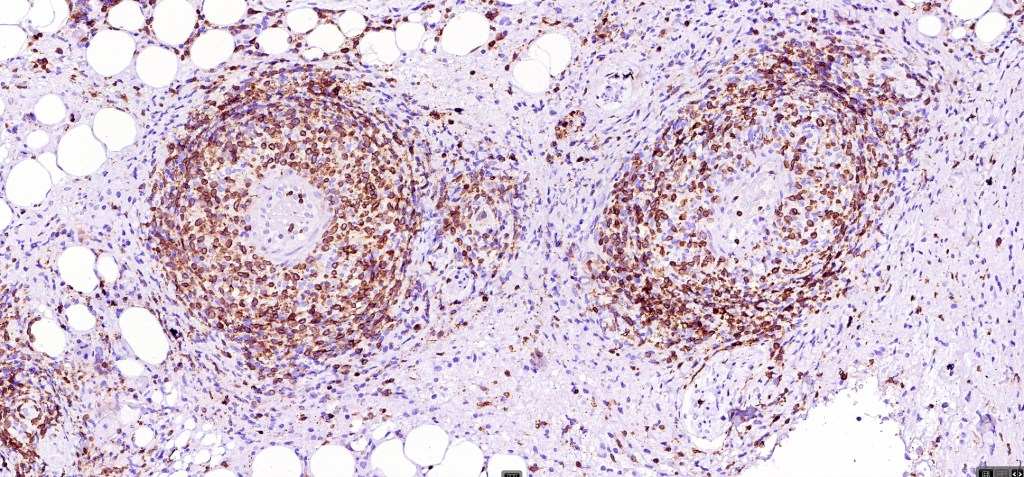

•CD4, CLA, MUM1 +ve

•CD45, CD30 +ve/CD15 –ve (types A & C)